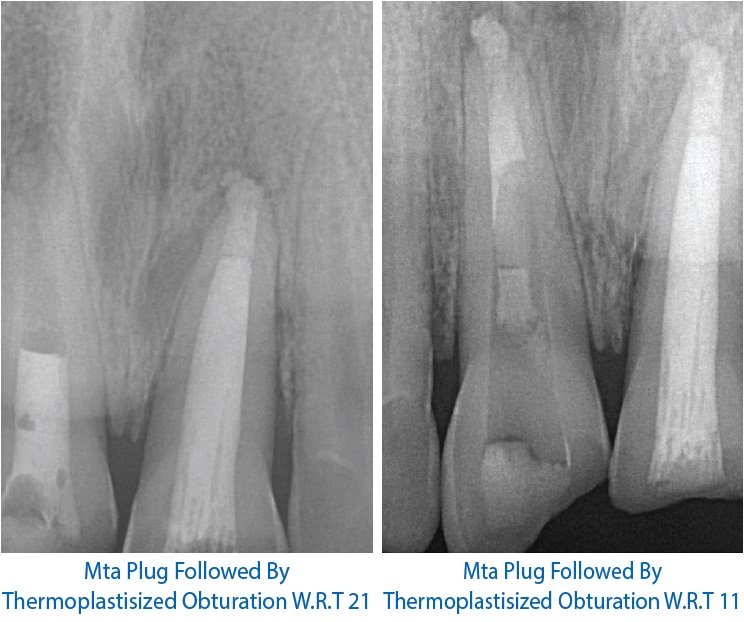

Nonsurgical endodontic retreatment of a maxillary central incisor with open apex using MTA Endodontic Apical Seal Root canal sealers seal off of the root canal system, entombing the remaining bacteria and filling irregularities in the prepared canal. Healing of apical periodontitis after endodontic treatment: Periapical lesions showed significant healing after endodontic treatment regardless of sealer type, although bioceramic and bioactive. Achieving a hermetic seal by entirely filling the root canal space decreases the risk that microorganisms. Endodontic Apical Seal.